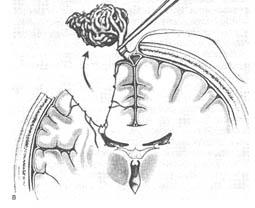

A klasszikus módja, hogy távolítsa el az AVM.